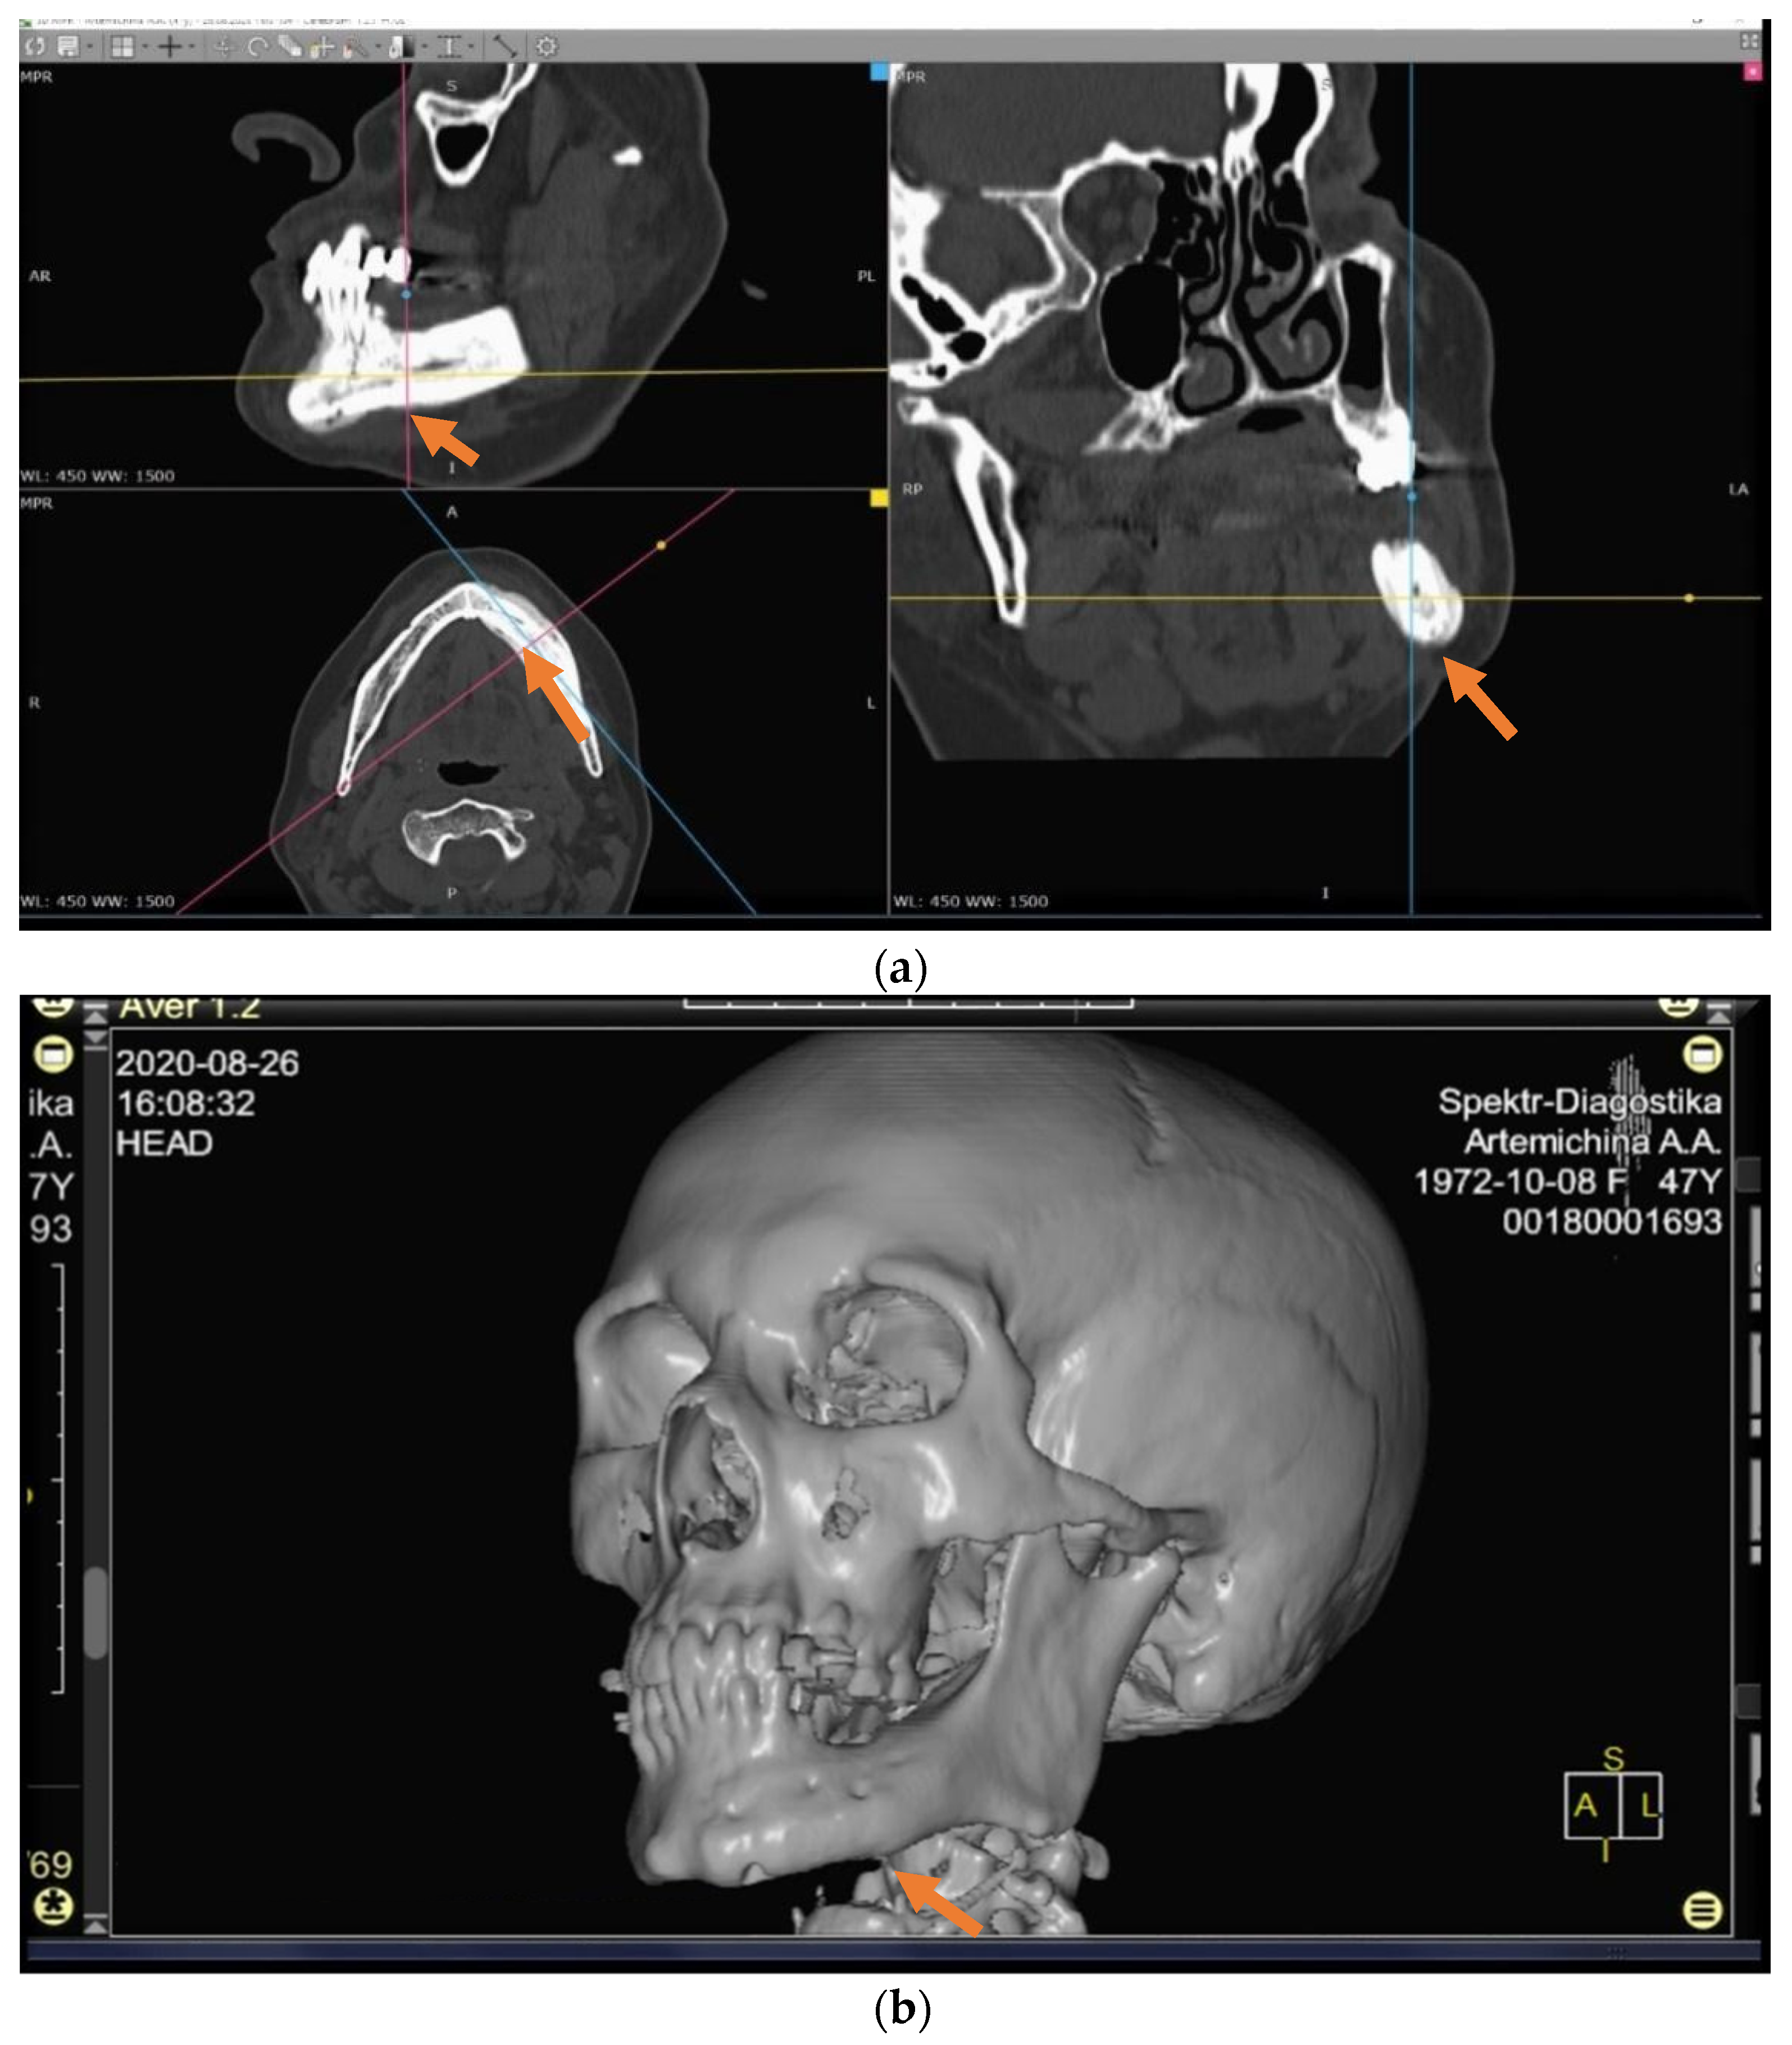

The patients in the main group (43 subjects) underwent segmental resection of the jaw after preoperative preparation (Figure 2 and Figure 3a,b).

Figure 1. (ad) Patient A: 47-year-old female. DS: Medication-related osteonecrosis of the jaw (the left side). Surgical treatment: Resection of the lower jaw on the left (9 September 2018).

Figure 3. (a,b) CT scan before operation (26 April 2018).